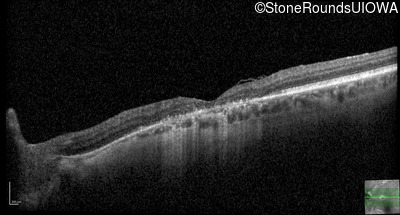

This 52 year old man had normal vision until his mid 30's when he began to have trouble distinguishing colors. the issuing 10 years he had a gradual loss of visual acuity accompanied by increasing photophobia.

| Age at visit: 55 years |

| Age at visit: 58 years |

| Age at visit: 61 years |

| Age at visit: 64 years |